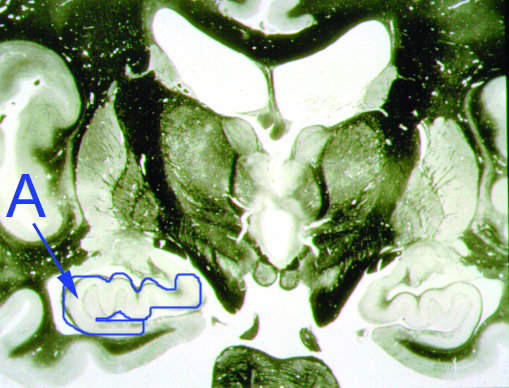

What is structure “A”?

Amygdala

What is the function of structure "A"?

Addictive behaviors center

Fear center

Consolidation of long term memory center

Rage behavior center

None of the above